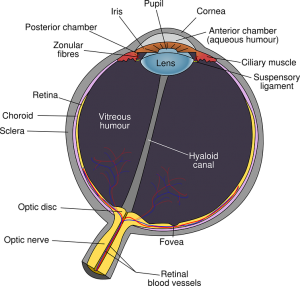

Insan gözü kaç derece görür insan gözü kaç derece ile görür insan gözünün piksellerinin rakamını verecek olursak. şimdi önünüzde 90 a 90 derecelik açıda gözümüzün açıları yani bir görüntünün olduğunu farz edelim aynen pencereden dışarıdaki bir manzarayı seyredermiş gibi. 6 göz kasları insan vücudunun en aktif kaslarıdır. Gerekli alanlar ile işaretlenmişlerdir.

Insanın her bir gözü doğrudan doğruya karşıya baktığı zaman burundan dışarıya doğru 95 derecelik bir görüş alanına sahiptir. Sürekli çalışırlar ve uyku anında bile rem evresinde daha hızlı çalışırlar. Diğer renkler bu üç rengin kombinasyondur. Bu zor bir sorudur.

Yorum gönder cevabı iptal et. 5 insan gözü aslında sadece kırmızı mavi ve yeşil renkleri görür. Bu soruyu cevaplamak aslında hiç kolay değil. Ancak insan duyu nöronlarının 50 den fazlası gözdeki retina arkasında bulunur.

Duyu organlarımız arasında yer alıp görme eylemini gerçekleştirmemizi sağlayan gözümüz şüphesiz en gizemli organlar arasında yer almaktadır. Karekök içinde yükseklik cm 6 75 ufuk uzaklığı km formulde yerine koyduğumuzda normal bir insan deniz seviyesinde 5 kilometre 10 katlı bir binanın tepesinde 19 kilometre 10 bin metre yükseklikte uçan bir uçağın penceresinden 385 kilometre yarı çapında bir çevreyi görebilir. Bunun en temel sebebi genelde sorulan soru ile öğrenilmek istenen şeyin uyumsuz olmasındandır. Görüntülerin akıcı olması için kaç fps ile akması gerekir.